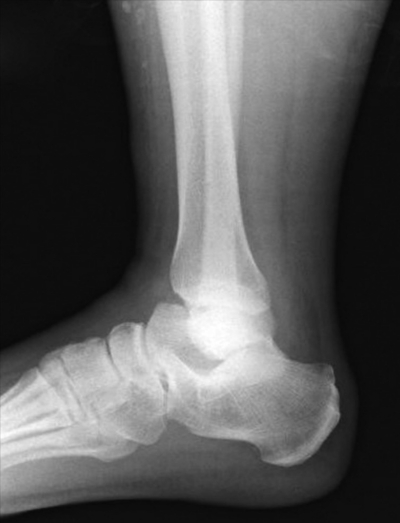

搬入時(受傷2時間後)の意識は清明。体温 36.9 ℃、心拍数 100/分、整。血圧 124/76 mmHg。呼吸数 14/分。SpO2 100 %(鼻カニューラ 1L/分酸素投与下)。右足関節全体に腫脹と圧痛を認める。右足関節周囲に開放創はない。足背動脈は左右差なく触知可能であり、右足趾の自動屈曲伸展運動は可能で、感覚に異常を認めない。右足関節以外に異常を認めない。右足関節単純エックス線写真を別に示す。